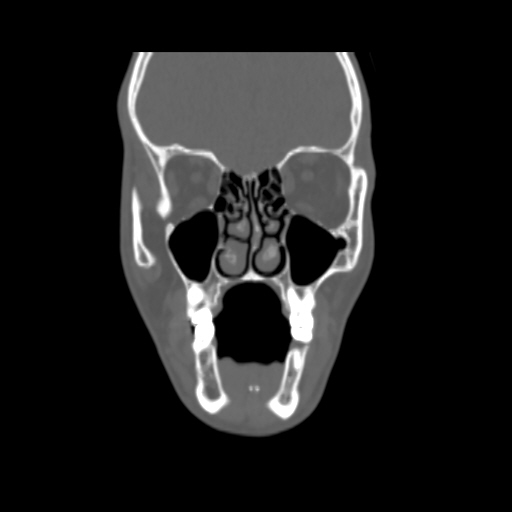

O/E images: